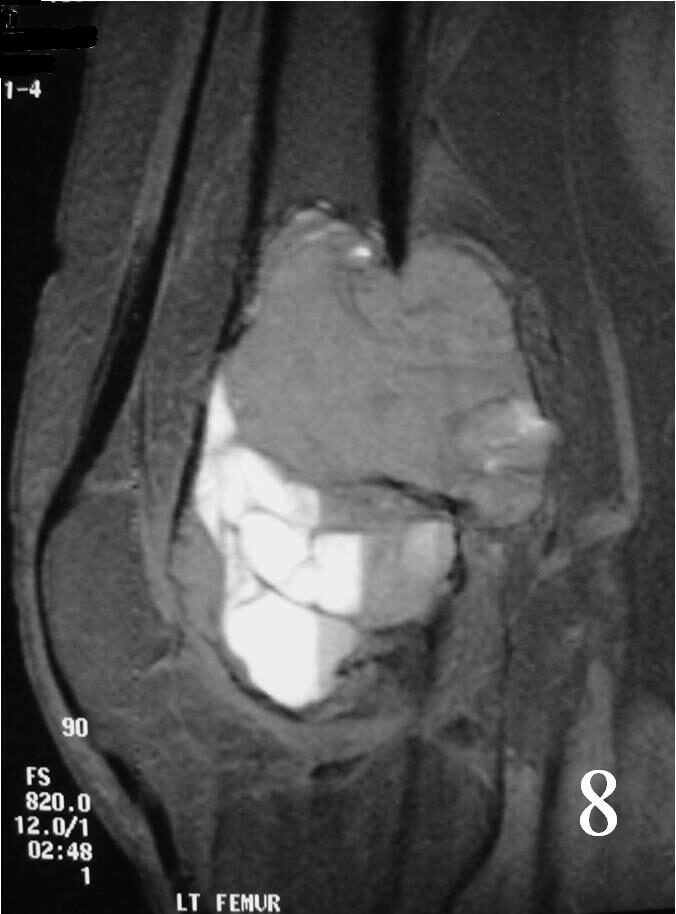

MRI

- Possible fluid-fluid level ( associated with secondary ABC) (Fig. 7, 8)

Fig. 8 Sagittal T2 MRI with fluid – fluid levels detected, indicative of ABC changes or secondary ABC component. There is posterior soft tissue extension. The soft tissue component is surrounded by periosteum.